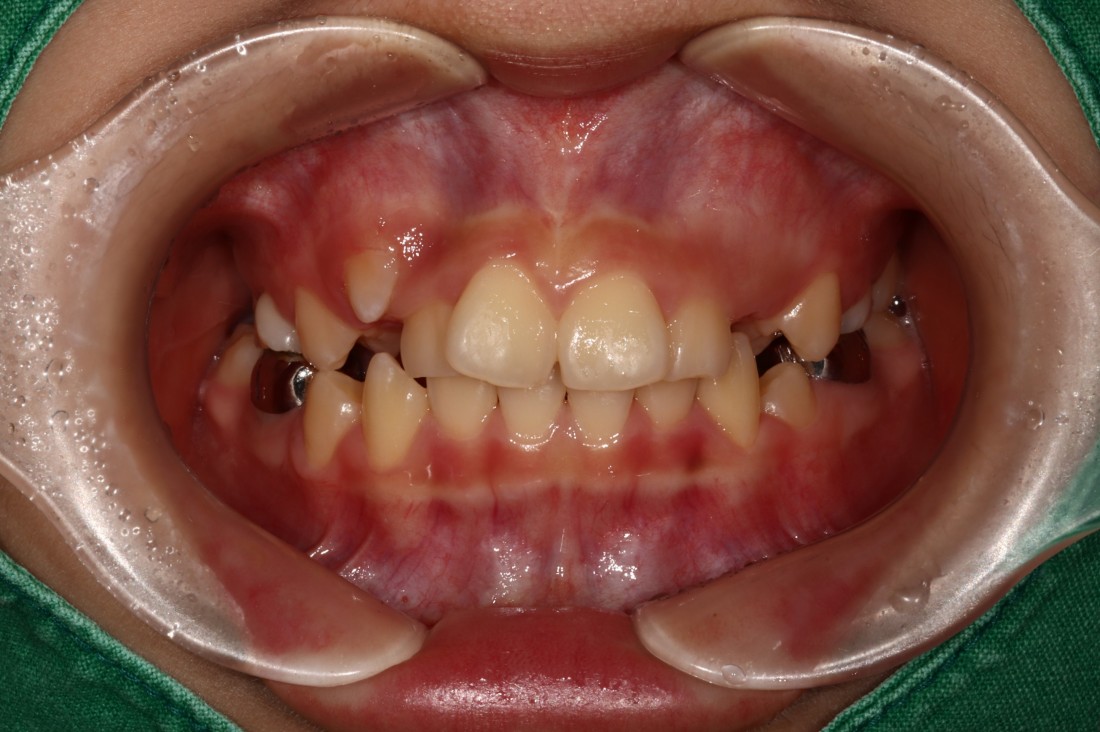

광주 덧니교정 치과에서는

덧니교정 시에

발치를 하는 경우도 있고,

비발치로 진행하는 경우도 있습니다.

치료계획은 모두 경험이 풍부한

교정전문의 대표원장님과

교정 전 정밀검사 결과를 토대로

오랜시간 세심한 상담 후에

결정하고 있습니다.

교정전문의가 봤을 때

발치가 꼭 필요한 경우가 있기 때문에

다양한 덧니교정 케이스와 비교하며

나만을 위한 치료계획을 세우고 있습니다.

![]() | ![]() |

광주 덧니교정 치과는

대표원장인 제가 직접

다양한 교정 전/후 케이스를

공유하고 있습니다.

다양한 각도에서 촬영한

교정 전/후 사진을 직접 확인할 수 있어

광주 덧니교정 치과의

실력있는 진료를 증명하고 있습니다.

발치를 진행한 덧니교정이나

비발치 덧니교정 모두

다양한 케이스를 보유하고 있기 때문에

나의 구강구조와 비교해보면서

성공적인 교정치료 결과를

기대해보실 수 있습니다.